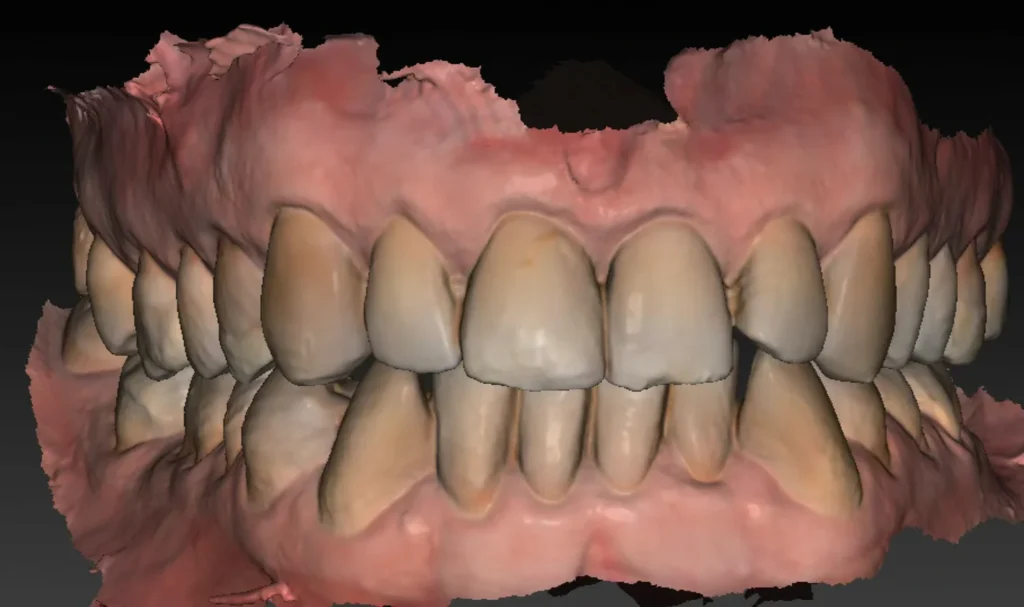

Une empreinte optique est également effectuée. Elle permet :

- de visualiser avec précision le relief gingival et d’identifier les zones nécessitant éventuellement une greffe de gencive ;

- d’évaluer les rapports occlusaux en vue de la future restauration prothétique ;

- d’alimenter la planification numérique en superposant les données optiques au volume osseux issu du Cone Beam.

L’ensemble de ces données permet ensuite de réaliser une planification implantaire précise, fondée sur une analyse tridimensionnelle croisée des tissus durs et mous, et tenant compte des exigences prothétiques.